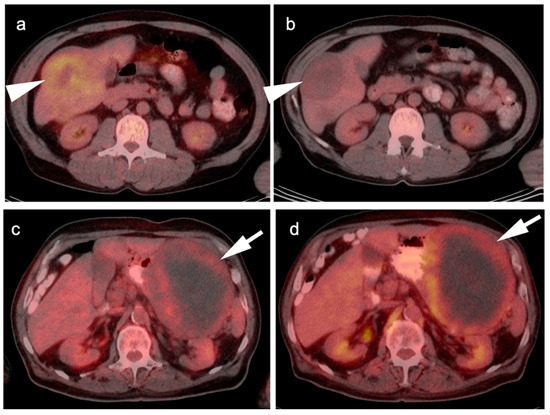

3. Gastrointestinal Stromal Tumor (GIST)

4. Hepatocellular Carcinoma

5. Cholangiocarcinoma

6. Gallbladder Carcinoma

7. Adrenal Cancer